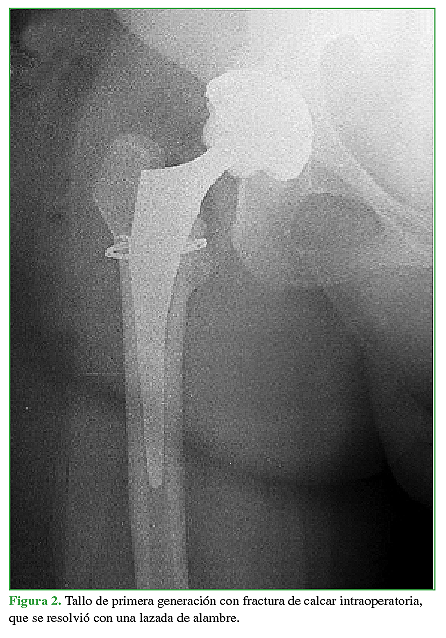

Al evaluar al grupo 1, contemplando el primer año de seguimiento posoperatorio, se produjeron dos (2,44%) complicaciones durante la cirugía. La primera fue una fractura de calcar, que se resolvió colocando una lazada de alambre en el mismo momento, evaluando la estabilidad inicial con la raspa de prueba y luego colocando el tallo definitivo (Figura 2). La segunda complicación fue una falsa vía generada mientras se trabajaba el canal femoral (Figura 3A), la cual se resolvió a las 24 h, en un segundo tiempo quirúrgico, con el correcto reposicionamiento del mismo componente primario (Figura 3B).

En contrapartida, no se produjeron complicaciones intraoperatorias con los tallos de segunda generación, pero sí con los de primera generación, una fractura de calcar y una falsa vía femoral, ambas mientras se trabajaba el canal (2,44%). Esto concuerda con los resultados obtenidos por Colacchio y cols., quienes reportan un 3,27% de fracturas de fémur intraoperatorias con tallos de primera generación y un 0,61% con los de segunda generación.12 Atribuimos esta diferencia en dicha complicación a una de las modificaciones más significativas en el diseño, como es el aumento del radio de curvatura de la cara medial, específico para cada tamaño de canal femoral. Esto permite un trabajo del canal que se ajuste más anatómicamente a él, evitando el impacto directo sobre el calcar, a medida que crece el tamaño de las raspas. Esto no es posible con los tallos de la generación anterior, ya que estos (al igual que las raspas correspondientes) modifican su tamaño solo a expensas de variar la cara lateral del tallo, su cara medial permanece con el mismo radio de curvatura.